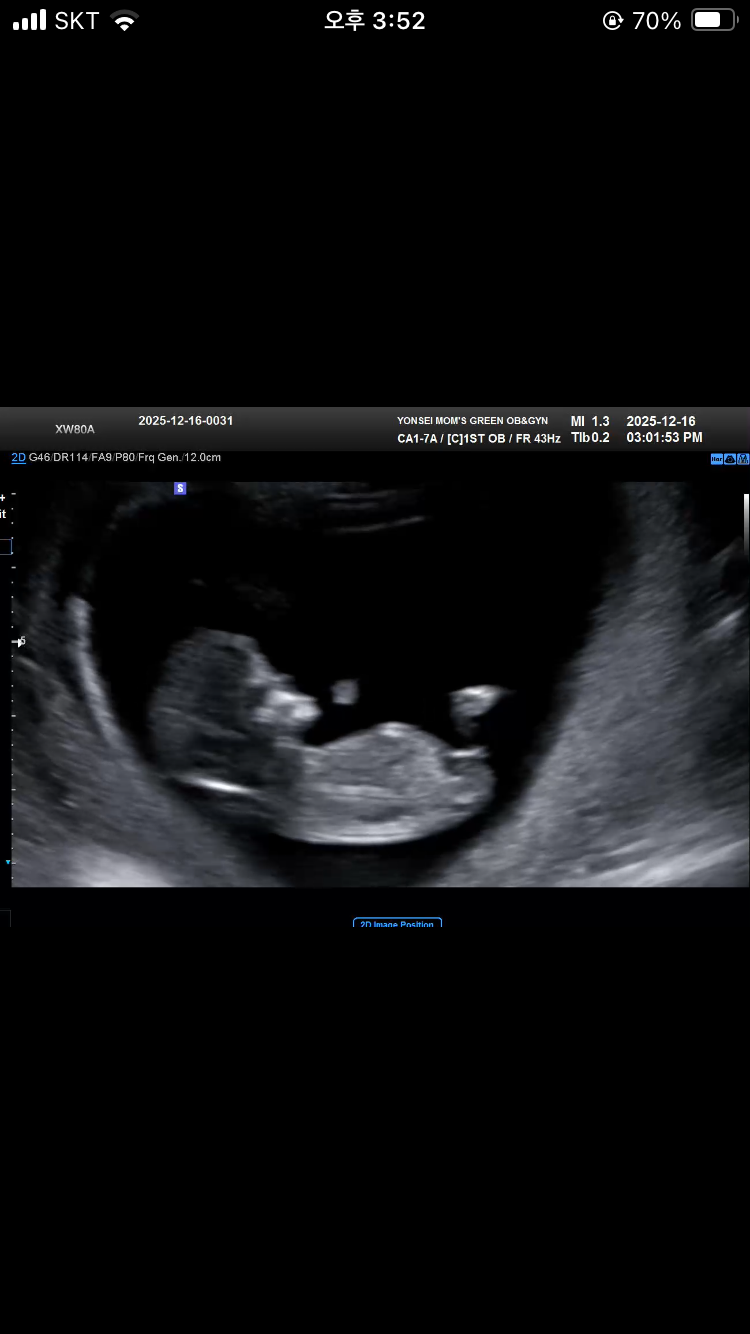

11주 3일 초음파 각도법 성별 봐주세용!

11주 3일 초음파에요~ 각도법 잘 보시는 분 계시면 성별 댓글 달아주세용!!